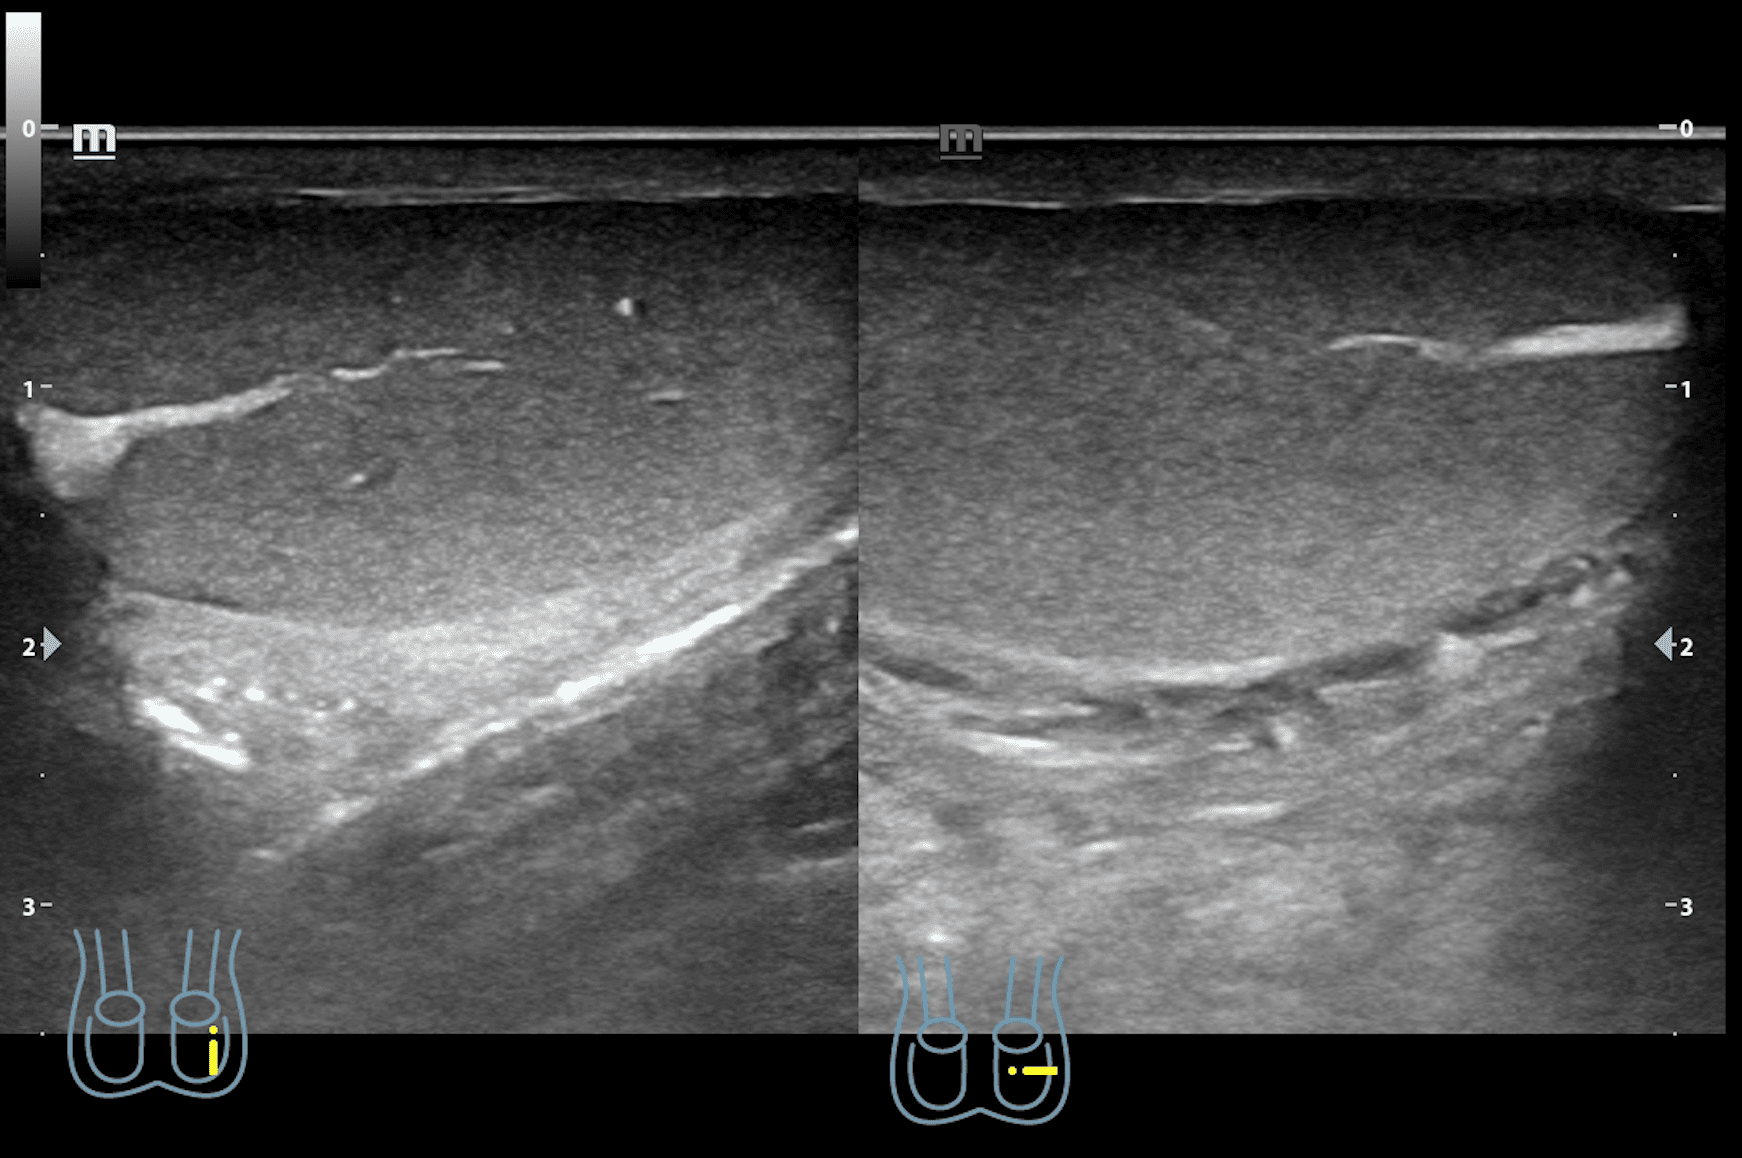

A nivel de escroto derecho, se observa imagen heterogénea con contenido intestinal compatible con hernia inguino-escrotal derecha. Testículos de aspecto normal.